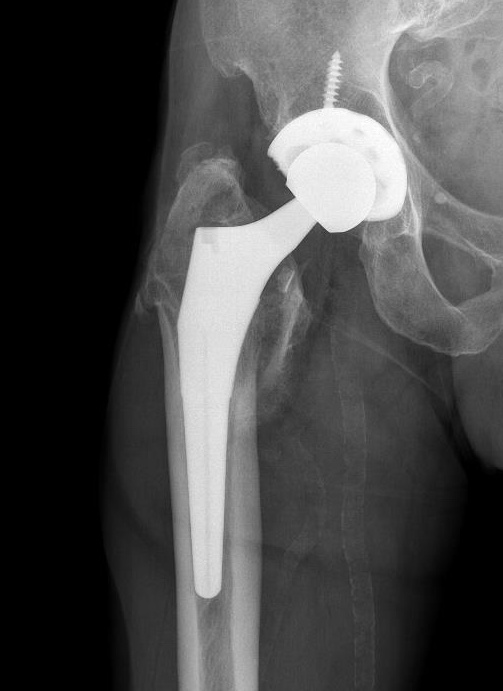

Long stem cemented revision